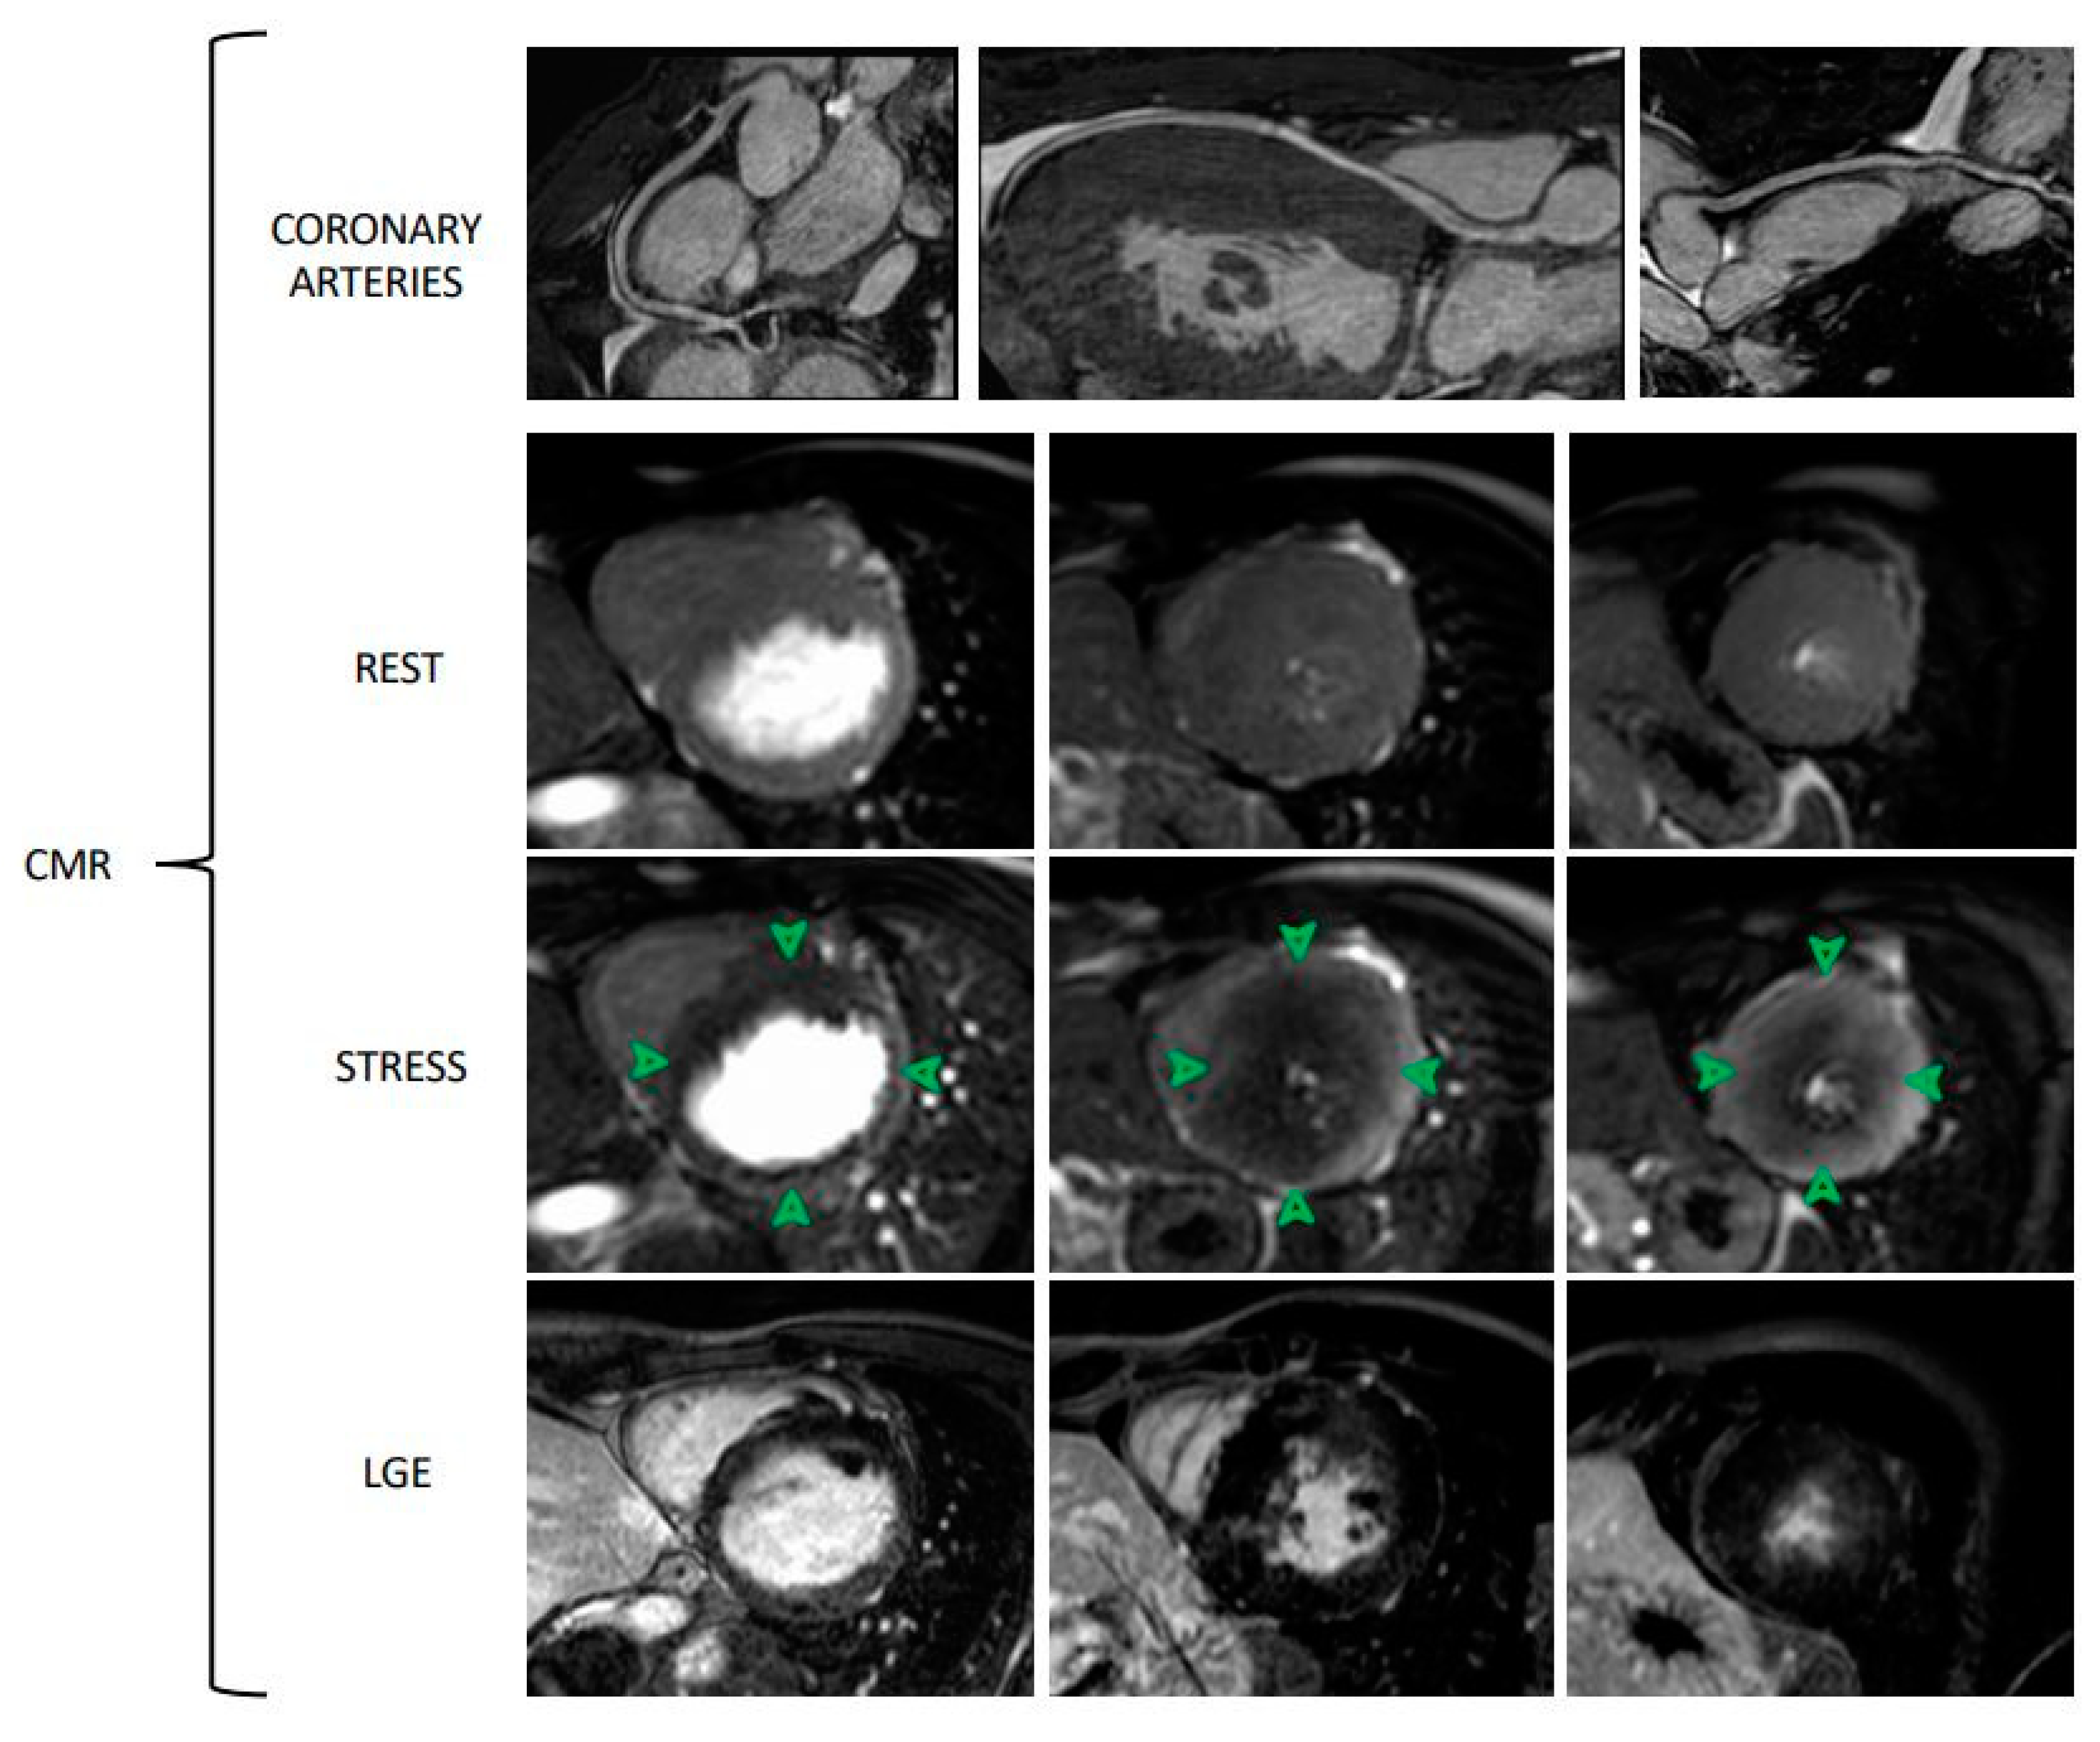

4. Cardiovascular MRI

| CMR | Vasodilator stress and rest perfusion images | -High spatial resolution -Tissue characterization -No radiation -Validated and compared with PET and invasive methods -Anatomic evaluation of epicardial coronary vessels (limited data) | -High costs -Limited by renal function -Limited availability -Poor prognostic data -Time consuming |